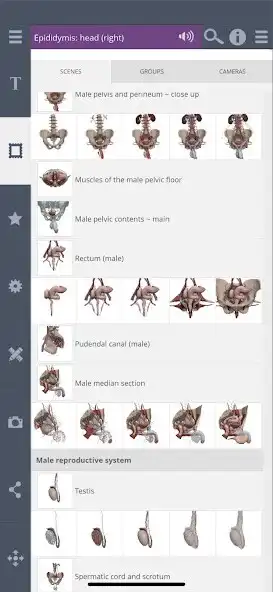

The Gallery contains 13 pre-set scenes, designed by an in-house team of anatomical experts, to clearly and comprehensibly present in-depth regional and systemic anatomy of the male pelvis. Each scene is divided into five layers to provide greater control over the depth of anatomy shown; making tailoring the anatomy you want to see simple and quick.

The Contents folders arrange all 405 structures systemically, meaning you can browse by subcategory and switch all related structures on at once. It provides an excellent learning tool for example turn on all branches of the internal iliac artery, or the muscles of the perineum.

The Contents layer controls split each system into five layers from deep to superficial. This allows you to quickly build up different systems to the depth you want to see.